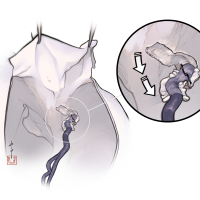

術後イラストシリーズ